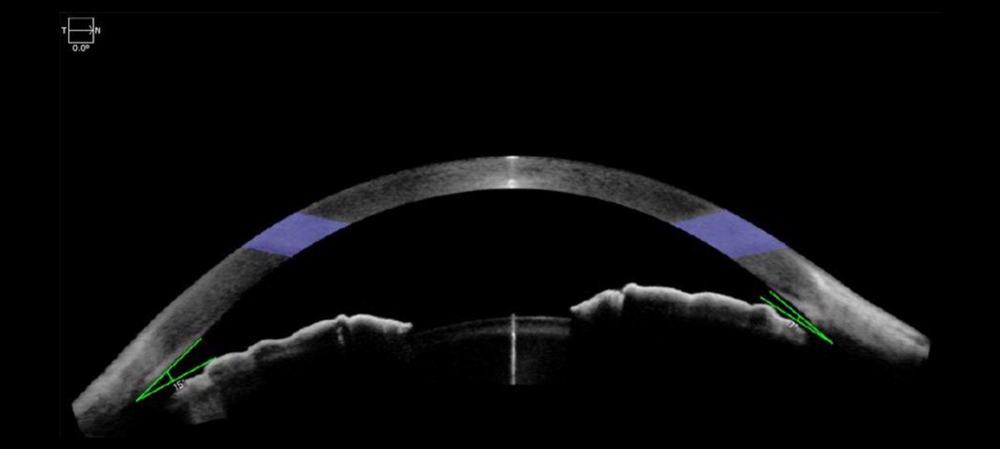

He offered this example: โIf an asymptomatic patient has anatomically narrow or closed angles determined during an eye exam, the imaging obtained would enable the physician to educate and counsel the patient of their condition, including intervention, as it would be difficult to explain to the patient otherwise. The image demonstrating angle closure would enable a provider to offer the patient options including 1) observation if asymptomatic; 2) laser iridotomy to open the drain as a preventative measure or if symptoms warrant the drain to be opened; 3) if appropriate, the need to perform cataract surgery to anatomically open the drain. This could also be a discussion in the setting of a patent iridotomy, yet the drain remains closed, and the patient is symptomatic with elevated eye pressure that needs to be lowered.โ

From a diagnostic standpoint, Dr. Shareef said imaging technologies can be helpful for patients who cannot have office-based gonioscopy, such as those who have a shallow or hypotonus eye. Imaging can help identify the location and size of cyclodialysis cleft for surgical planning, for example, or angle closure in the setting of a patent iridotomy in the presence of plateau iris syndrome. โ[Imaging] would enable the physician to counsel the patient to consider argon laser iridoplasty to further open the angle to enhance outflow and lower the eye pressure,โ Dr. Shareef said.

โOne challenge to performing gonioscopy is that itโs qualitative. We describe the structures we can see but we canโt take a precise measurement. It becomes hard to track conditions like angle narrowing or angle closure over time,โ he said. โOCT has been around for several decades, and itโs widely used in the posterior segment for measuring anatomical structures like the thickness of the retina. We and other research groups have been adapting OCT for the anterior segment as a means of more precisely quantifying the anatomical configurations of our patients. I think that is a unique strength of OCT, which nicely complements a primary weakness of gonioscopy. In addition, OCT is fast; it doesnโt take a trained clinician to perform; itโs non-contact so itโs comfortable for patients. Analysis of OCT images can also be automated using other technologies, such as artificial intelligence. In these ways, OCT may fill a clinical need for a more convenient and reproducible method to assess the angle.โ

Some knowledge from the research being produced with AS-OCT for angle imaging is being transferred to the clinic already. Dr. Xu said he and colleagues compared AS-OCT and gonioscopy for predicting patients with mild angle closure who would go on to develop more severe angle closure.2 They found patients with narrow angles on AS-OCT had a higher risk of progression, whereas gonioscopy was not as predictive. He added they have yet to identify specific cutoffs at which a patient should be considered higher risk and receive treatment, but this research is underway.